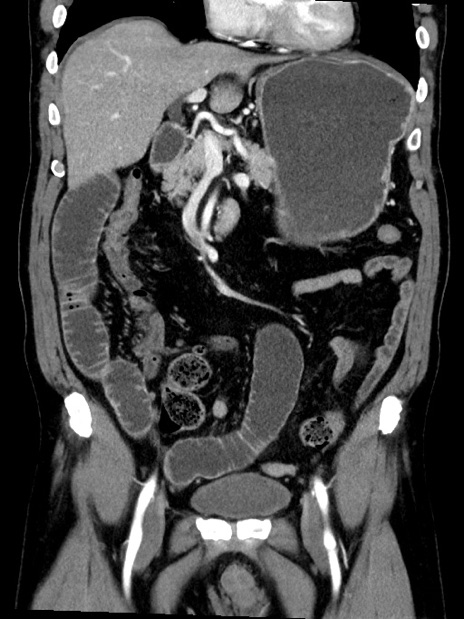

症例35(冠状断像)

【症例】70歳代 男性

【主訴】腹部膨満、嘔吐

【現病歴】昨日より腹部膨満感出現。本日増悪し、仙痛出現。嘔吐あり、受診。

【既往歴】糖尿病、胆摘後

【身体所見】BP 149/80mmHg、HR 74/min、BT 35.9℃、腹部:膨満、軟、圧痛なし。腸雑音減弱あり。上腹部正中切開瘢痕あり。

【データ】WBC 13500、CRP 1.72